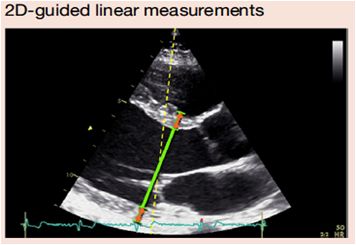

2、二维灰阶超声心动图

1、可以调节声束方向;

2、帧频低;

3、一维,仅代表形态正常的左室内径。